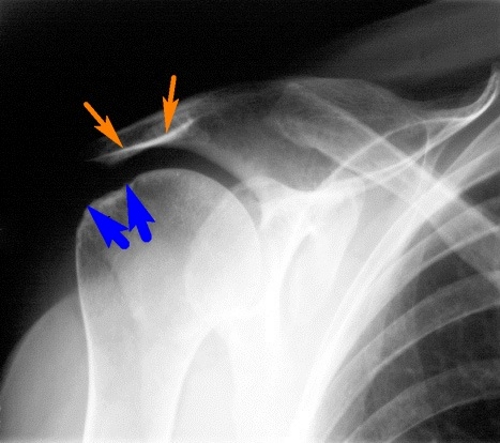

Выявление плечевого артрита начинается с осмотра и опроса пациента. Это позволяет оценить степень выраженности двигательных нарушений и обнаружить признаки атрофии мышц. Особое внимание специалист должен обращать на хруст. Если при обследовании обнаруживается симметричный характер поражения, речь идет о ревматоидном артрите. Лечение направлено на устранение причин, по которым может воспаляться плечевой сустав.